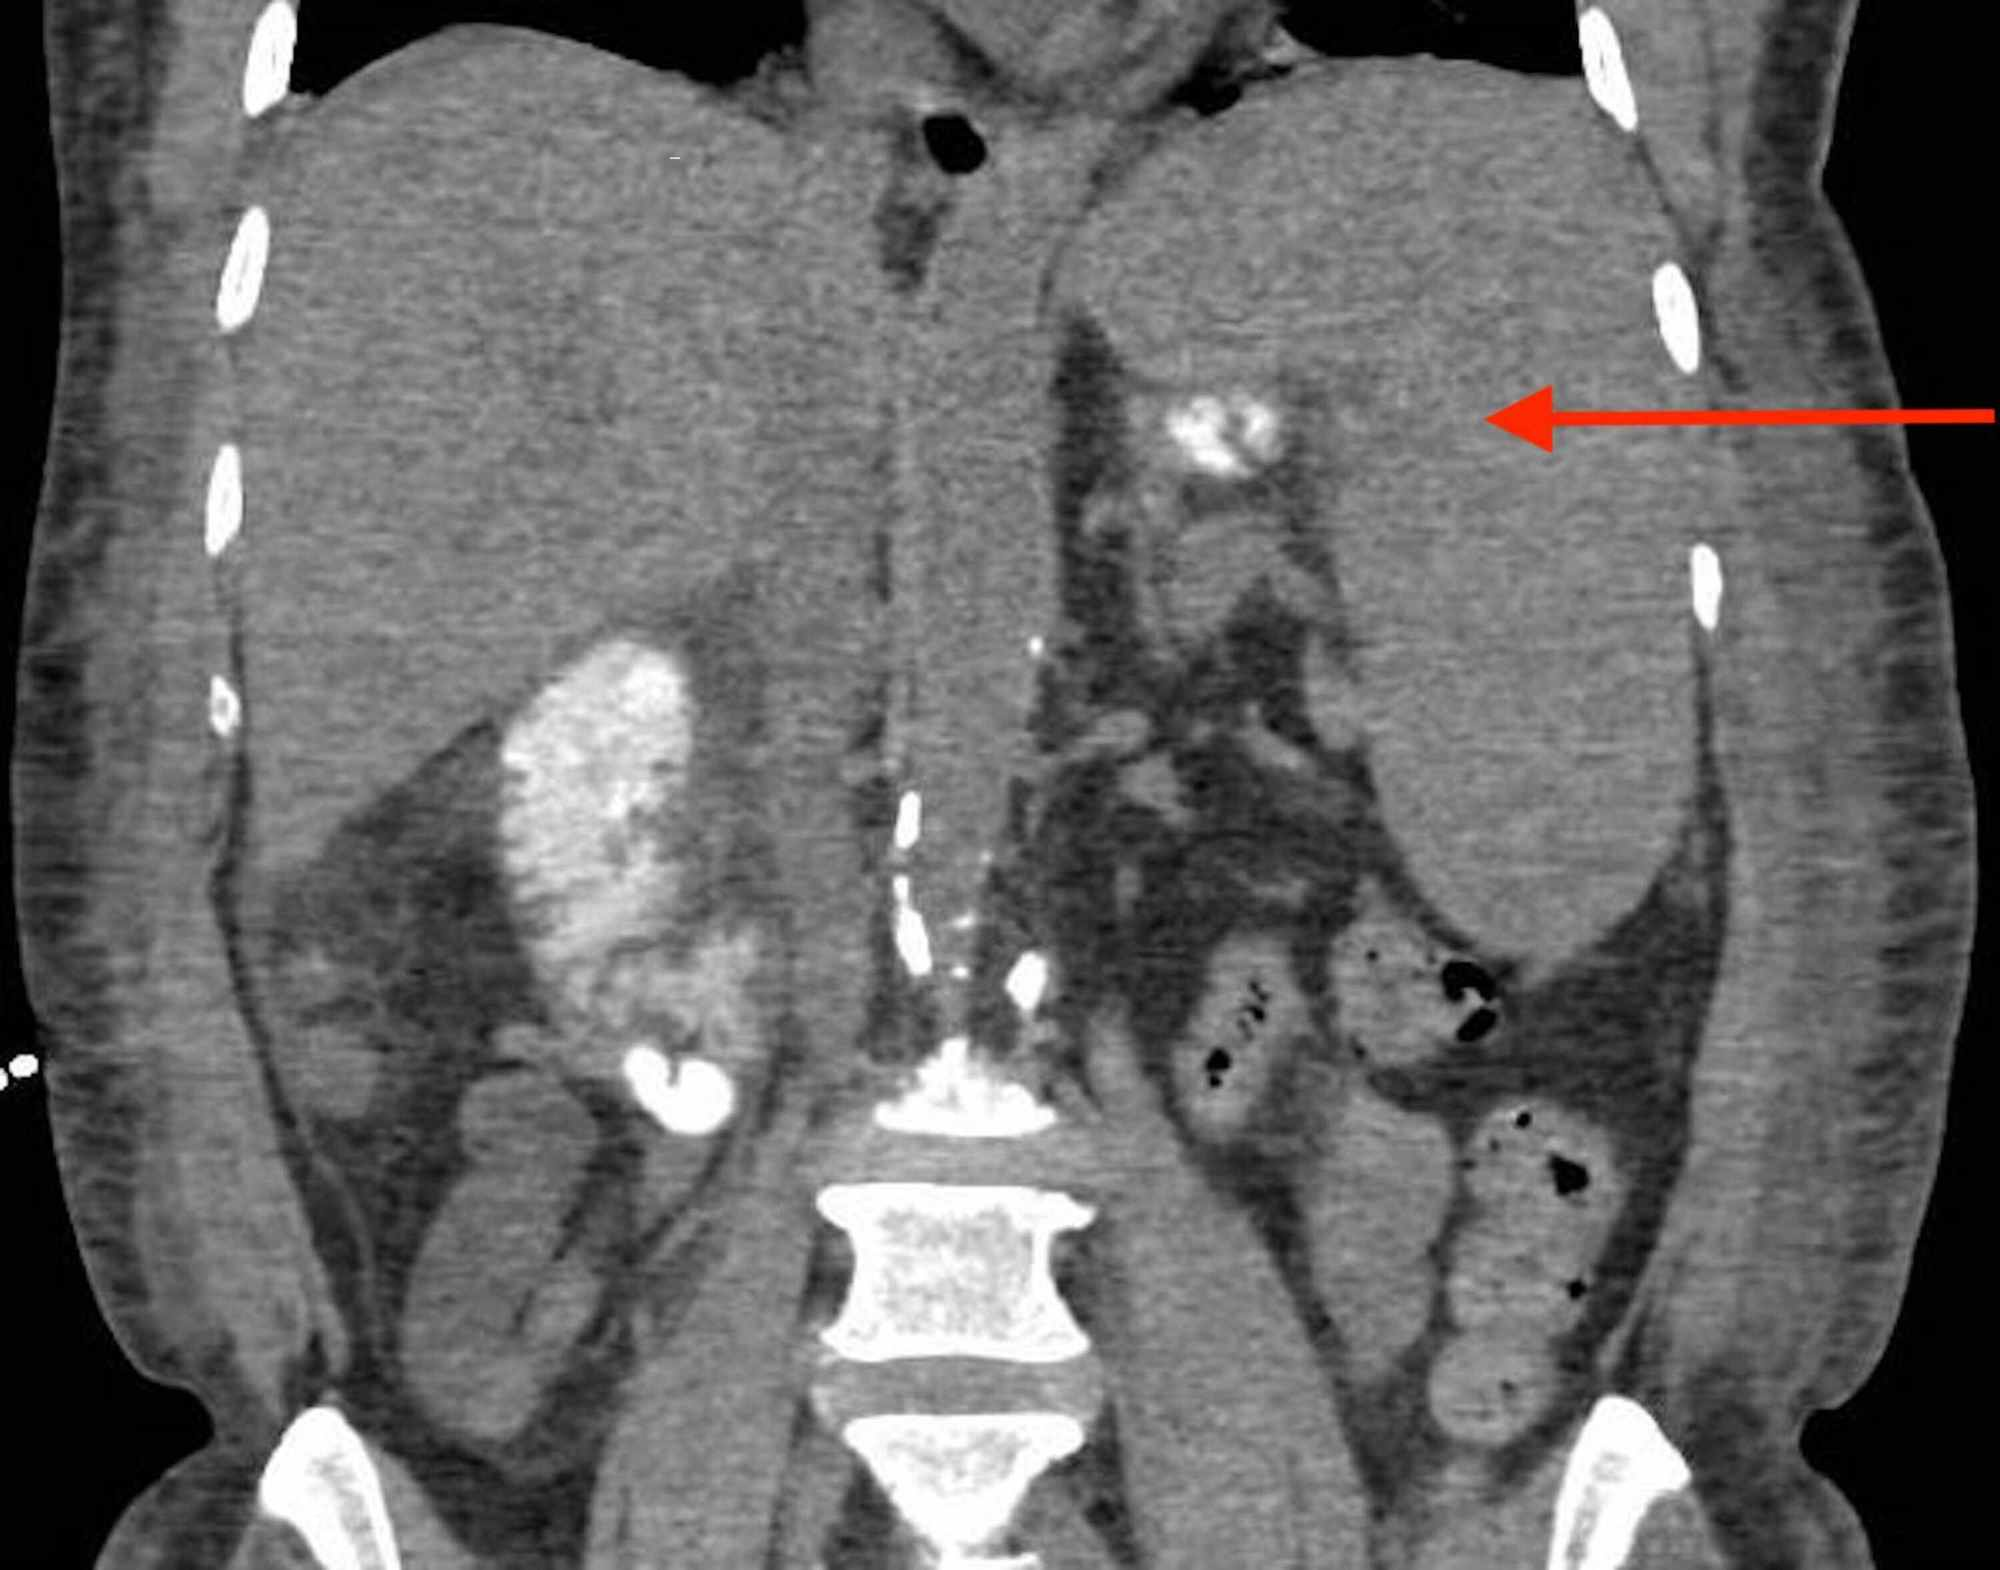

Initial infectious workup, including blood cultures, urine analysis, and chest x-ray, was negative. Further infectious workup with atypical/viral panel, Epstein-Barr viral capsid antigen antibodies, hepatitis viral panel, human immunodeficiency virus (HIV) antibodies, Mantoux test, acid fast bacilli cultures, fungal cultures, urine histoplasma antigen, and cytomegalovirus IgM antibody were all negative. Imaging including transthoracic echocardiogram and transesophageal echocardiogram showed no abnormalities. CT of the abdomen revealed splenomegaly of 17 centimeters (cm) (Figure 1). Antibiotics were then discontinued as infectious workup was negative.